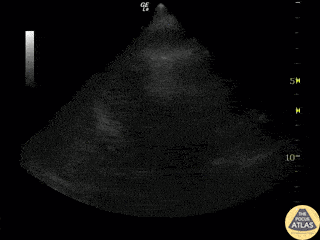

What view is this?

The subxiphoid/subcostal view is the primary echocardiography view used in the FAST exam to obtain a quick view of the heart. The other views might be used in further examination of the heart, if warranted or if the subxiphoid view is for some reason not accessible.